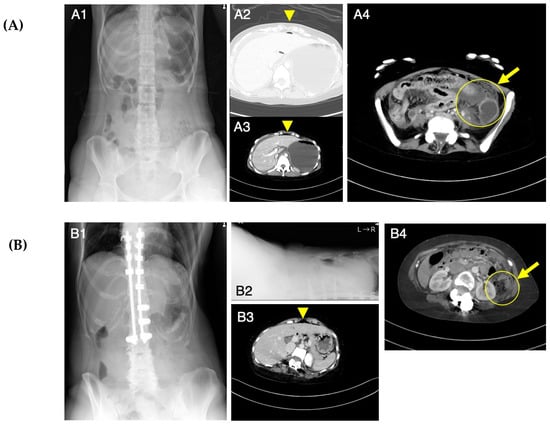

3.1. Detailed Course of Colonic Perforation